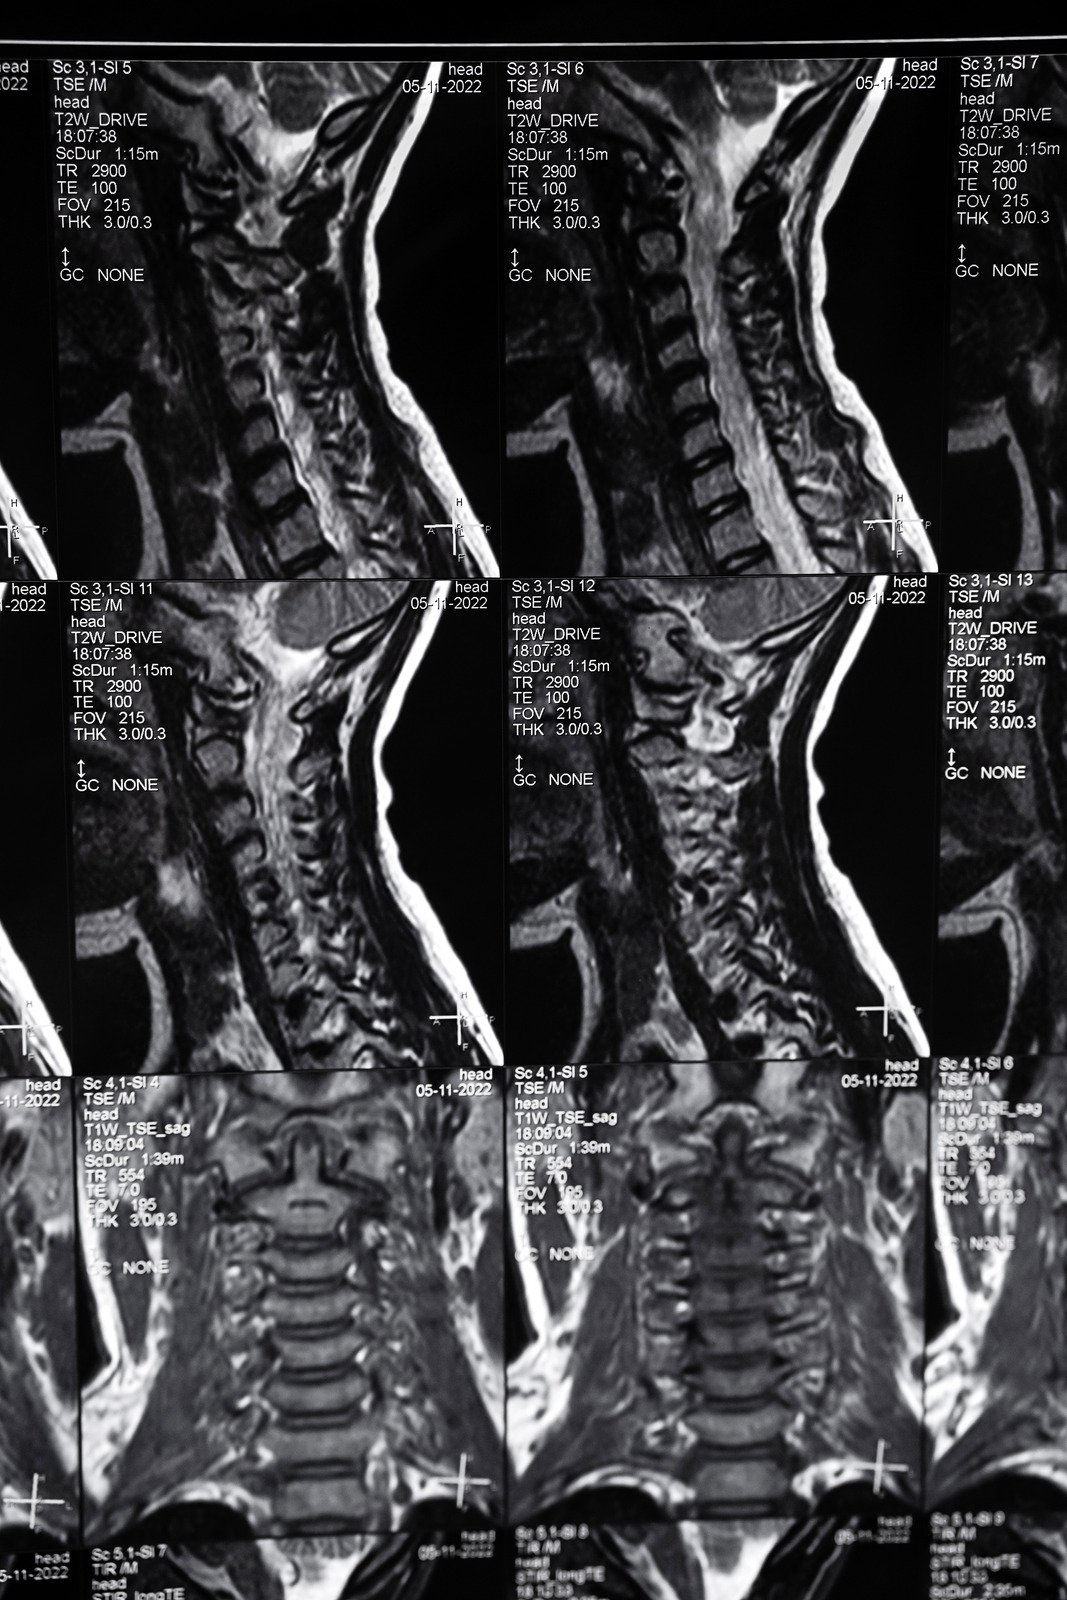

경추 디스크 질환 이해하기

경추 디스크 질환은 목 부위의 척추 사이에 있는 디스크가 손상되어 발생하는 상태입니다.

척추 디스크는 척추뼈 사이에 위치하여 충격을 흡수하고 척추의 움직임을 원활하게 해주는 역할을 합니다.

이 디스크가 탈출하거나 손상되면 주변 신경을 압박하여 목 통증, 팔 저림, 근육 약화 등의 증상을 유발할 수 있습니다.